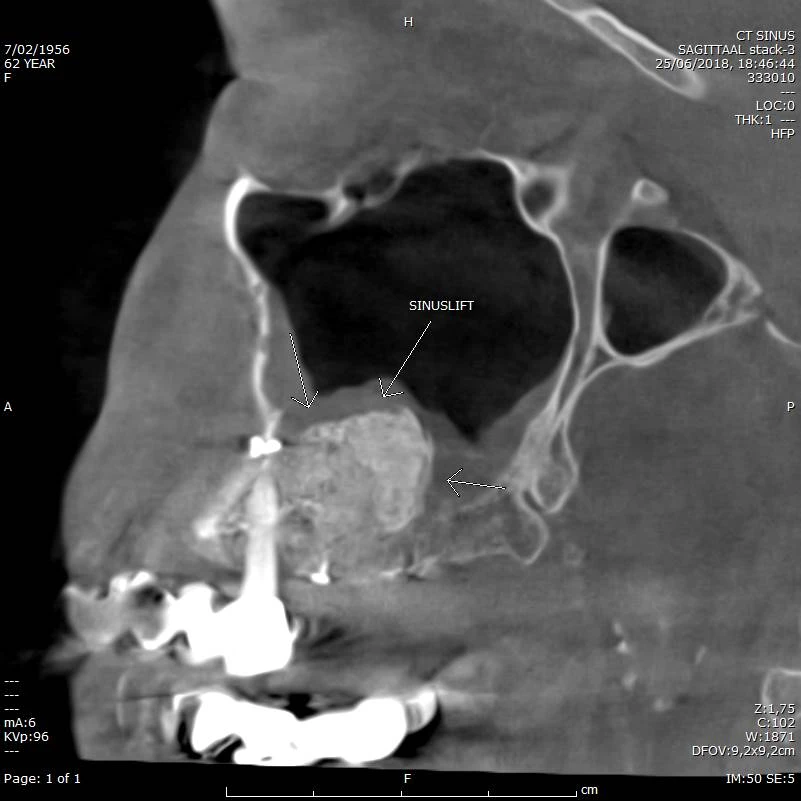

Follow up na Sinus Lift rechts (met veel metaal maxillair en mandibulair)

CBCT voorbeeld 7: sinuslift sagittaal

Sagittale doorsnede: sinuslift rechts, follow-up na ingreep